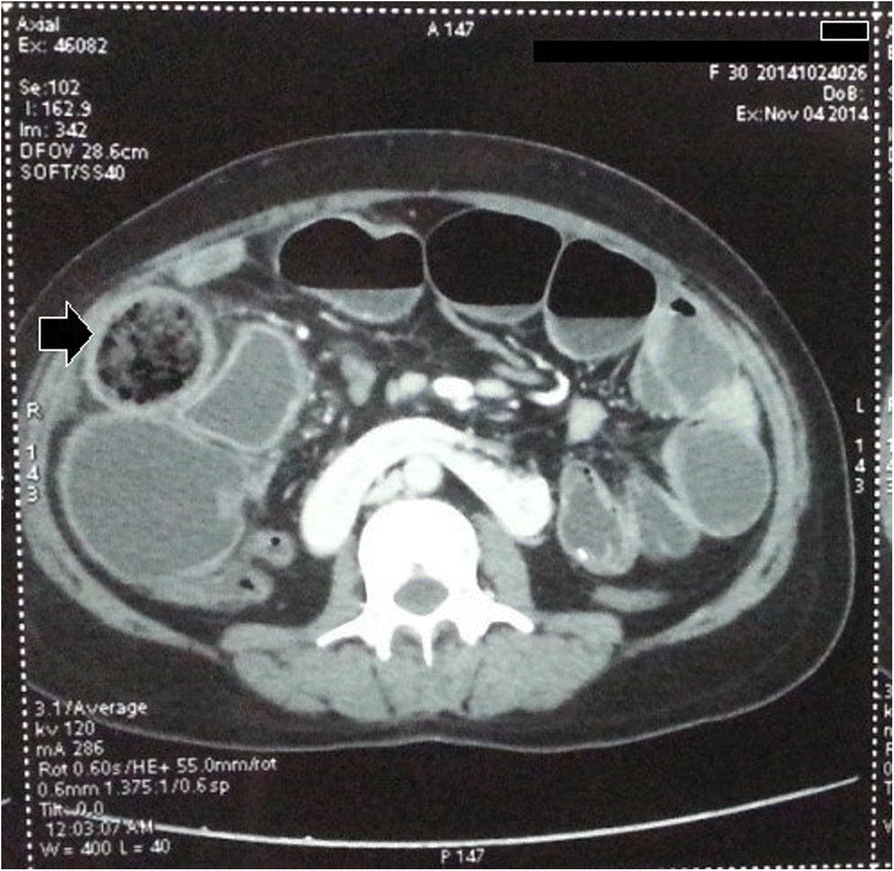

Computed tomography of the abdomen, showing intraluminal gossypiboma (Black arrow)